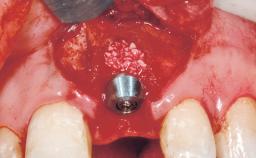

Immediate Flapless Placement of an Implant in a Maxillary Left Central Incisor Site

A 29-year-old female patient presented for treatment to replace the upper left central incisor tooth with an implant- supported restoration. The tooth had been intermittently symptomatic for the previous 12 months. The tooth had originally suffered trauma about 15 years previously. Several endodontic treatments had been performed, including an apicectomy procedure to retain the tooth. The patient was healthy and a non-smoker. She had reasonable expectations in regard to esthetic outcomes and the risk of marginal tissue recession following treatment. At medium smile, the gingival margins of the upper teeth were visible, with a display of 3 to 4 mm of the gingival margins. Gingival recession of tooth 21 and a discrepancy in the gingival levels between teeth 11 and 21 was observable during normal speech and smile.

Placement Protocol Immediate implant placement

Tooth Site Maxillary incisor or canine

Socket Morphology Single-root socket

Socket Integrity Damage to one or more bone walls

Bone Volume Damage to one or more socket walls